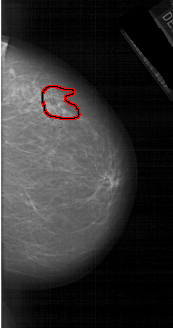

FILE: A_1986_1.RIGHT_MLO.OVERLAY

TOTAL_ABNORMALITIES 1

ABNORMALITY 1

LESION_TYPE MASS SHAPE IRREGULAR MARGINS ILL_DEFINED

ASSESSMENT 4

SUBTLETY 4

PATHOLOGY MALIGNANT

TOTAL_OUTLINES 1

BOUNDARY